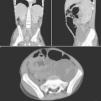

On day 3, he started a 6-month course of anti-tuberculous therapy due to a positive polymerase chain reaction (PCR) sample of Mycobacterium tuberculosis (Mt) in a gastric aspirate. This infection was later confirmed by a positive sputum culture. Meanwhile, a cervical nodular biopsy revealed necrotic areas along with others containing numerous histiocytes with multinucleated giant cells, polymorphic inflammatory infiltrate, and numerous uninucleate thick-walled large yeasts, budding from a narrow base (Fig. 1, arrow). Based on this morphology, a diagnosis of Hcd infection was made and he began therapy with liposomal amphotericin B (5mg/kg/day). Histoplasmosis was later confirmed by multiple positive swab cultures of the exudates. After 4 weeks of amphotericin B therapy, he was switched to oral itraconazole (10mg/kg/day). At this stage, a small clinical improvement was observed, with only minor reduction in the size of lymphadenopathies. In the following weeks, the patient clinical status was rapidly deteriorating, with enlargement of the previously noted adenopathies, along with appearance of new cutaneous fistulas. A painful supra-pubic abdominal mass appeared, and abdominal CT identified numerous new retroperitoneal lymphadenopathies and left hydronephrosis due to direct compression of the ureter (Fig. 2). Amphotericin B was restarted, with no apparent clinical benefit.

After approval by our hospital's ethics committee, posaconazole therapy was started, at a dosage of 400mg twice daily. A dramatic and lasting improvement, both clinical (Fig. 3A-D) and biochemical, was observed. Imagiologic control 2 months after introduction of posaconazole demonstrated resolution of hydronephrosis and only minor (1cm) lymphadenopathies. At day 127 of posaconazole therapy, complete cicatrization of all skin lesions was achieved (Fig. 3). Our patient completed 12 months of therapy with posaconazole. No relapse was noted during or 3 months after treatment.